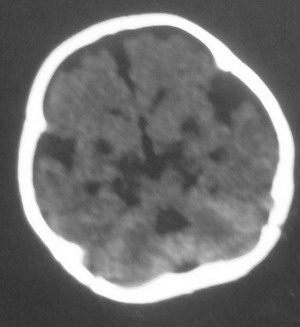

以下是引用dyqct在2008-7-30 17:05:00的发言:[br]考虑:1、胼胝体发育不全;[br] 2、肝豆状核变性(双侧豆状核对称性低密度)。

以下是引用杀毒软件在2008-7-29 17:53:00的发言:[br]考虑:胼胝体发育不全,额叶皮质及脑室旁白质萎缩.